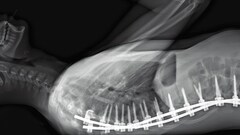

あらすじ・ストーリー 人体は、身近でありながら現在もなお神秘のベールに包まれている。パリ北部近郊の5つの病院を舞台に、ハーバード大学の人類学者の監督コンビが、医師の目線でカメラや内視鏡で内臓や外科手術の様子を映す。その生々しさは、生命力と美しさを持っていて……

解説 カンヌ国際映画祭監督週間に正式出品されたドキュメンタリー。パリ北部郊外の5つの手術室を舞台に、臓器や手術の様子を医師の視点から見つめる他、死と隣り合わせの職場に勤める医療従事者や、霊安室で行われる仕事内容などが映し出される。監督は、ハーバード大学感覚人類学研究所のルーシャン・キャステーヌ=テイラー、ベレナ・パラベル。